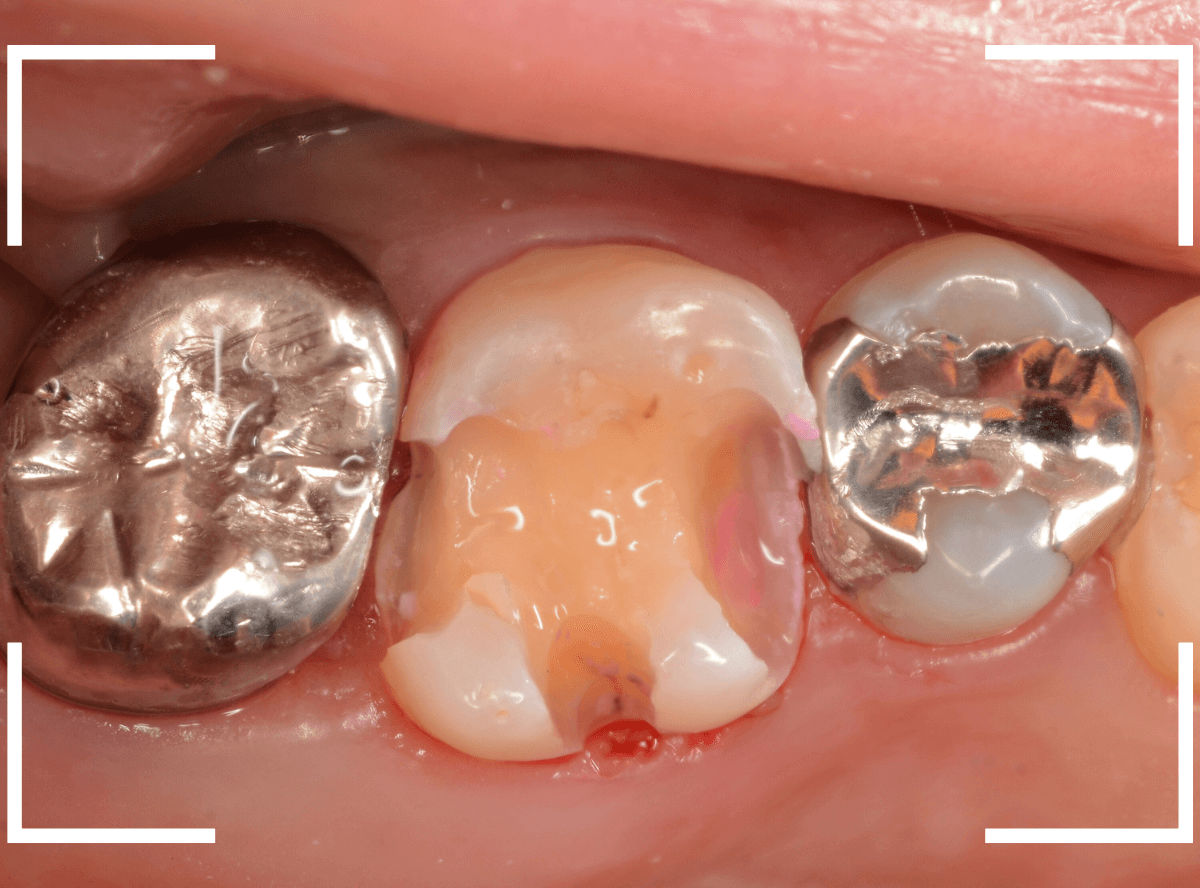

Case.14 噛むと上の奥歯が痛い

「噛むと上の奥歯が痛い」という症状で来院された患者さんです。

打診(ピンセットなどで歯を叩き比べて、痛みの原因の歯を診断する方法)で矢印の歯が痛い事がわかりました。

レントゲン写真で確認します。

レジンの下の赤い色の線が虫歯であろうと思われる部分です。

痛みのある歯については、なんとも微妙な写り方に見え、虫歯だと断言し難い状況でした。

このような場合は、症状とレントゲン写真などから推察していくのですが、痛みは噛んだ時のみで、虫歯特有のしみるなどの症状がないため、そこからも判断しづらい状況でした。

あとは、虫歯と思われる部分を削りながら調べていくしかありません。

患者さんに状況をお話しし、レジンを除去して調べてみると、診断通り、虫歯が出てきました。

虫歯をある程度除去したところです。

まず、一番左の〇部、隣の銀歯との間になにか固いものがはさまっています。

物を噛んだ時に痛むのはこれが原因の気がします。

中央の〇部、赤く染まっている部分は虫歯がまだ除去しきれていない部分です。思ったよりも深めの虫歯です。

一番右の〇部は、メタル・インレーのつけ根に虫歯が小さく顔を出しています。

痛みのある歯の虫歯をすべて除去し、はさまっていた物も全て除去したところです。

手前の歯のメタル・インレーを除去し、虫歯を除去すると、その手前の歯のレジンも不適合なのが見つかりました。

全ての虫歯を除去したところです。

思っていたよりも広い虫歯でした。

しばらくお薬をつめて、経過観察をします。